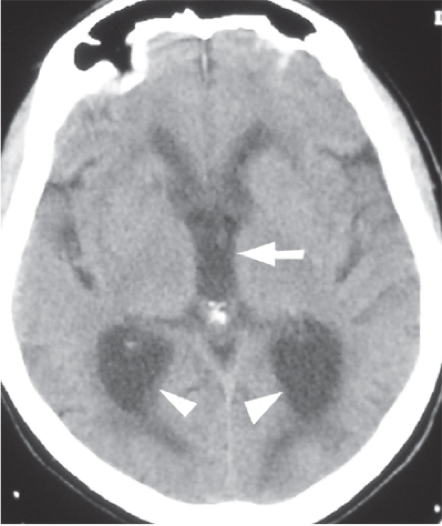

• Figure 2.10. CT of patient w/ normal pressure hydrocephalus. Note the dilated atria of the lateral ventricles (arrowheads) and rounded third ventricle (arrow) on this image. This is from a patient with normal pressure hydrocephalus. Neurosurgery, Brunicardi F, Andersen DK, Billiar TR, Dunn DL, Hunter JG, Matthews JB, Pollock RE. Schwartz’s Principles of Surgery, 10e; 2014. Accessed: July 27, 2018.